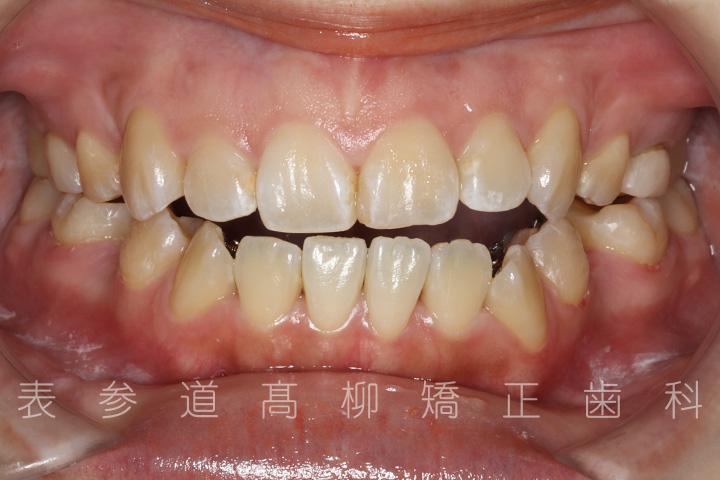

前歯のガタガタ感と開咬でお悩みの患者様の症例をご紹介いたします。

・前歯部開咬

・上下前歯部叢生(凸凹歯並び)

術前術後の比較